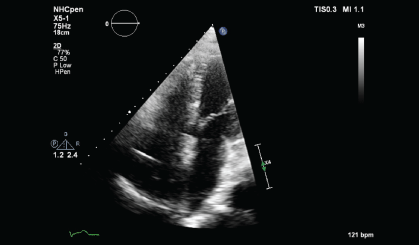

A CT guided biopsy of the right supracondylar femur showed intertrabecular fibrosis with small clusters of CD 163 and CD 68 immunopositive foamy macrophages. No giant cells, eosinophils, or features of Langerhans cell histiocytosis were present. S100, CD 1a immunostaining were negative, and BRAF v600e was positive. These features were consistent with ECD. A two-dimensional echocardiography performed showed a normal left ventricular ejection fraction of 70% with a right atrial mass of 2.5 × 1.3 cm at the posterior wall and another at the lateral wall, which was not visualized on the PET-CT performed. During the course of his stay, a pacemaker was inserted as he developed ventricular fibrillation and bradycardia with sinus pause associated with multiple episodes of syncope.

Figure 4a: Transthoracic echocardiogram (TTE) showing mass lesion in the right atrium close to the tricuspid valve and at the posterior wall (June 2013).

Figure 4b: TTE showing persistent mass lesion in the right atrium close to the tricuspid valve and at the posterior wall (March 2014).

Upon histopathological confirmation of ECD, the patient was given subcutaneous peginterferon-α of 180 mcg once/week and prednisolone of 1 mg/kg/day. After 3 months of treatment, his shortness of breath and joint pain resolved. Repeat laboratory test showed declining ESR of 29 mm/hr and a repeat PET-CT scan showed significant improvement in pericardial soft tissue thickening encasing the thoracic aorta and coronary arteries, with skeletal lesions also showing quantitative reduction of the metabolic activity (Figure 3a and Figure 3b) and no new hypermetabolic lesions. (Table 1). A repeated two- dimensional echocardiogram 18 months later showed regression of the right atrial mass (Figure 4a, Figure 4b, Figure 4c and Figure 4d).